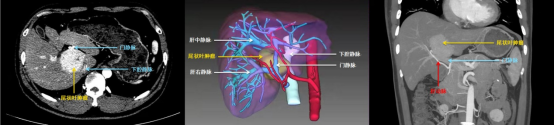

术前影像学、3D立体成像显示,尾状叶肿瘤包绕在肝部大血管中

原来,王先生的肝肿瘤位于肝脏的尾状叶,肝尾状叶曾经一度被称为外科手术的“禁区”,其后方是下腔静脉,前方是左、右肝蒂,上方更是有3支肝静脉包绕,腹腔内最粗的血管几乎都在此处经过,稍有不慎就可能会造成术中大出血,甚至会有死亡的风险。经多方打听,王先生找到陆朝阳,希望能在微创下切除肿瘤。陆朝阳团队发现,王先生的门静脉已经被肿瘤压迫至严重狭窄,如肿物继续增大进一步压迫门静脉,则可能会导致浮肿、腹水、脾大甚至呕血等症状。

开腹手术会给患者留下巨大的手术疤痕,而尾状叶切除即使是开腹手术也极其困难。考虑到年轻患者的迫切希望,秉承“最有利”患者的伦理原则,陆朝阳团队选择了手术难度大,但对手术创口小的微创技术进行手术。团队术前通过3D立体成像技术精确评估,反复推敲设计手术路径,最终在麻醉科、手术室、腹部超声科等团队的合作下,陆朝阳团队经5小时的奋战,依靠成熟的微创手术技术和丰富的手术经验,仅仅通过腹壁上的6个小孔就将肝脏及主要肝血管精准游离,顺利在全腹腔镜下实现全尾状叶完整切除,整个手术出血量不到100ml,腹部切口仅有5cm。